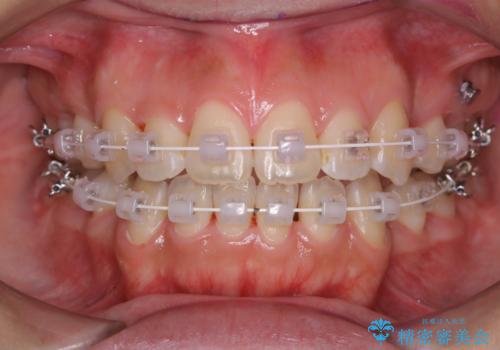

ワイヤー矯正中のクリーニング

担当医 歯科衛生士